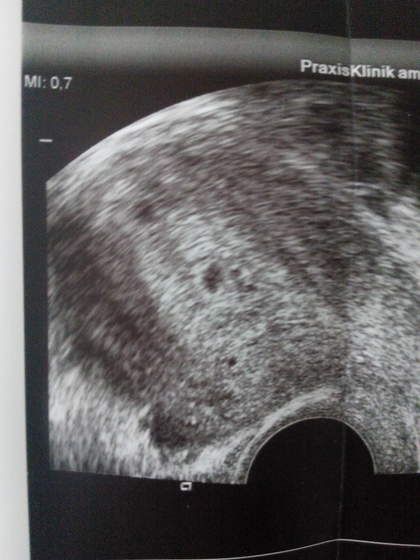

A wiec moje kochane ja juz po usg . Ciaza sie rozwija a oto efekt ..

Zobacz załącznik 702968

Blizniaki :)

Podstawowym badaniem stwierdzającym obecność zespołu jest badanie usg. Najczęściej obserwujemy postać lekką zespołu, w której stwierdza się powiększone jajniki, których średnica czasem osiąga kilkanaście centymetrów. Pacjentka może odczuwać dolegliwości bólowe, nie obserwuje się zaś płynu w jamie brzusznej. Leczenie polega na kontrolnych badaniach usg jamy brzusznej, codziennej ocenie masy i bilansu płynów oraz podaniu leków przeciwbólowych i przeciwwymiotnych.